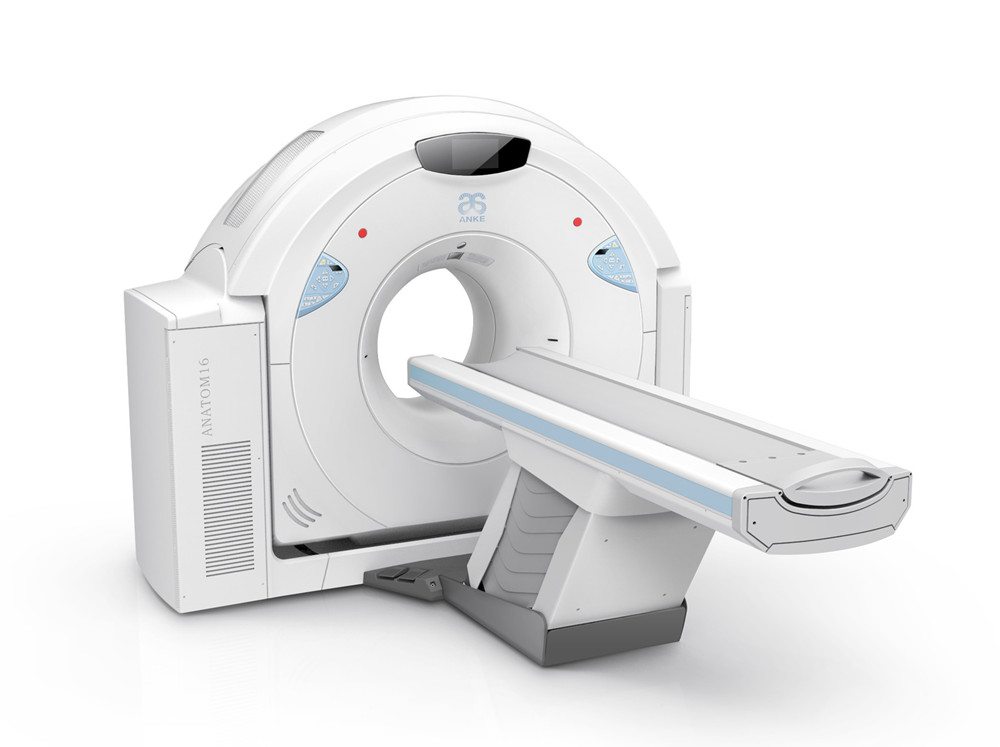

案例展示 ∥ 影像类设备 ∥ ANATOM 16层螺旋CT

作为国内资深的CT生产厂家,该机型具备了与国际主流产品相同的技术能力,为此需要开发全新的产品外观及结构,以适应新的产品形象。大型医疗器械涉及到材料,力学,工艺,运动机构,人机功效等不同的各种学科知识,无限空间设计团队为了整合不同学科要求而做出平衡性设计,同时突出设计亮点,为产品赋予自身特有的产品形象。

ANATOM 16层螺旋CT是针对国内基层医疗机构对高端CT的需求而推出一款划时代产品,采用了十多项创新性技术,它对于我们国内广大县乡日益增加的肿瘤、心脑血管疾病等诊断有着重要意义,凭借卓越的影像质量,ANATOM 16可以帮助医生进行早期、微小病变以及心脑血管疾病等全身各个系统的诊断及筛查,进而给患者及时恰当的治疗,为患者的早期治疗赢得时机。

客户 | 安科医疗

项目 | ANATOM 16层螺旋CT

年份 | 2013

client | ANKE Tech

year | 2013